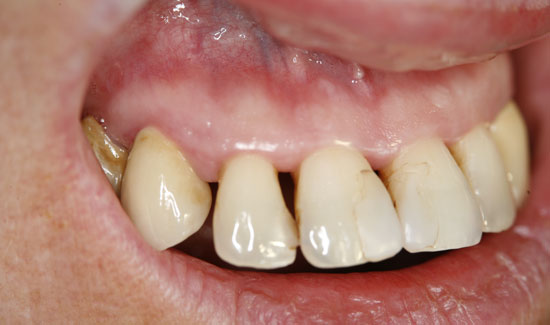

Abb. 1: Orthopantomogramm